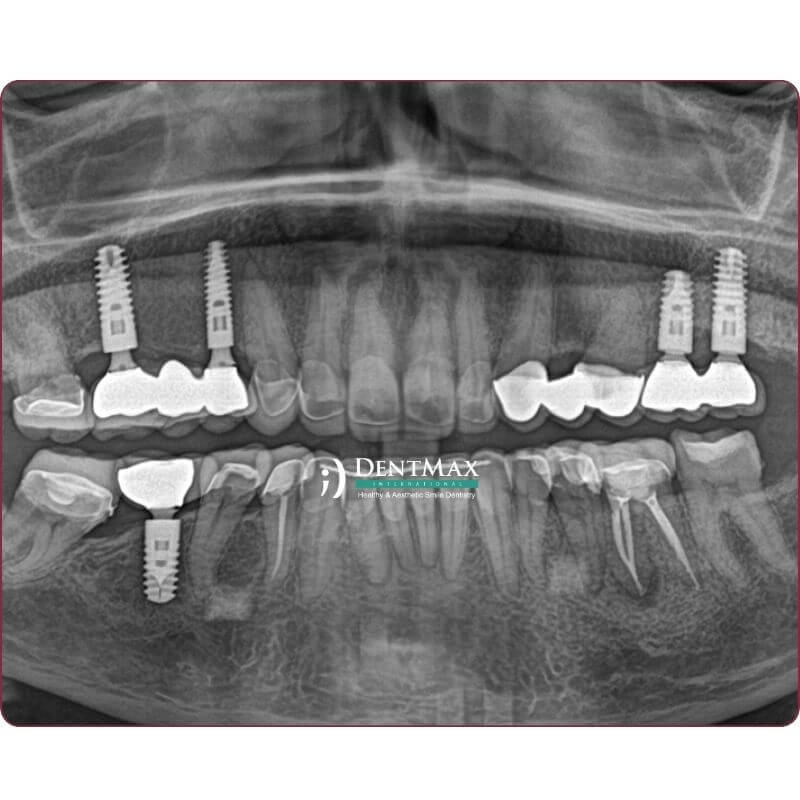

Faz I - Cerrahi Aşama